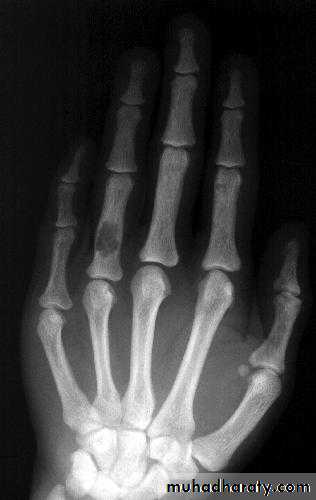

(Bone resorption is virtually pathognomonic(Subperiosteal resorption

Radial aspect of middle phalanges

(especially index and middle finger)

Tunneling of MCP bones (nonspecific)